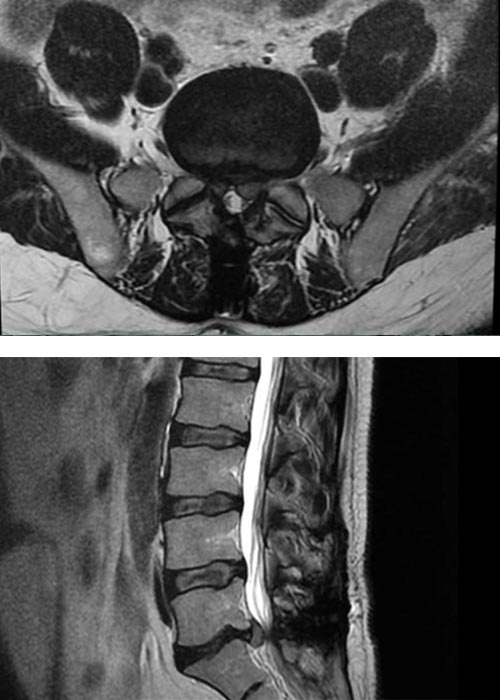

Preoperatorio

Caso de recidiva de Hernia discal en Madrid, operada previamente mediante cirugía abierta

preoperacion-recidiva-hernia-discal-en-madrid